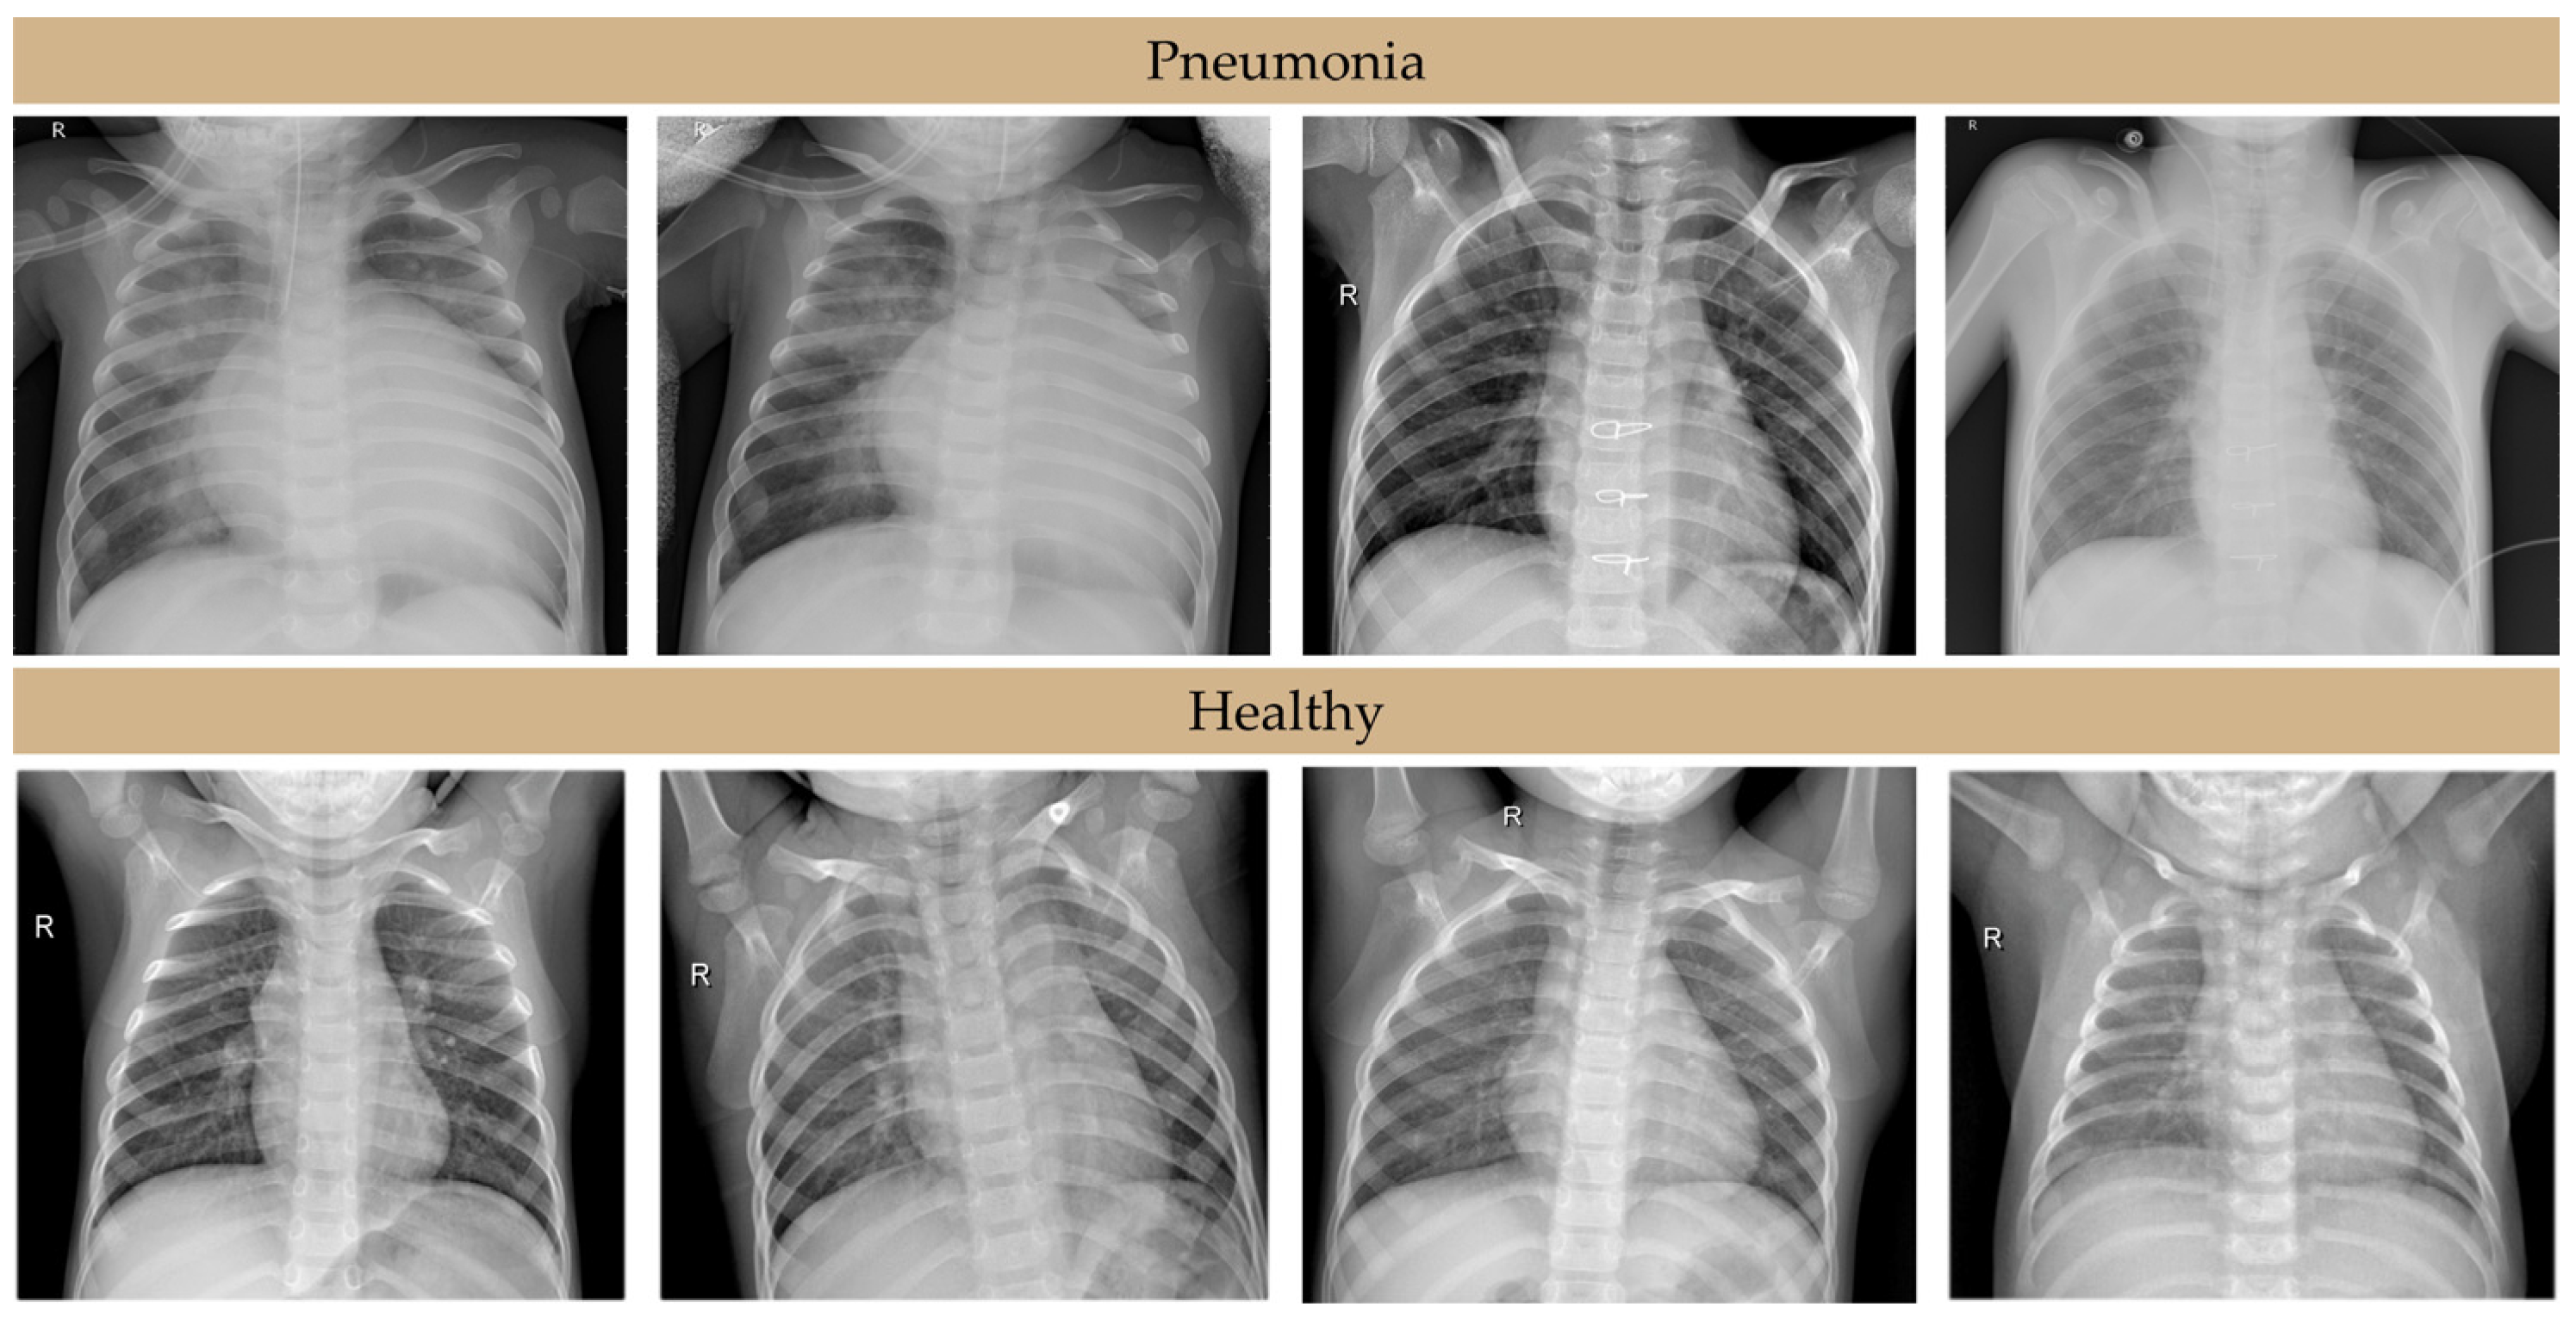

To further validate the model, enhance interpretability, and facilitate clinical integration, Gradient-weighted Class Activation Mapping (Grad-CAM) was employed. Grad-CAM generates visual explanations by producing heatmaps that highlight the image regions most salient to the model’s classification. In our architecture, this technique was applied to the last convolutional layer to ensure that the extracted features were both spatially and semantically rich. This technique is particularly valuable in the context of pediatric pneumonia diagnosis, as it offers transparency into the model’s decision-making process, enabling verification of its diagnostic rationale and fostering clinical trust. In healthy cases, Grad-CAM typically generates diffuse activation patterns across the lung fields, consistent with the absence of focal pathology. Conversely, in cases of viral pneumonia, Grad-CAM heatmaps demonstrate more distributed and heterogeneous activation, often encompassing perihilar regions and reflecting the characteristic interstitial infiltrates associated with viral infection. In contrast, bacterial pneumonia exhibits more localized and intense activation patterns, concentrated over regions of consolidation, aligning with the typical lobar presentation of bacterial infection. The results are presented in Figure 4.

Figure 4. Grad-CAM heatmaps demonstrating model focus in pediatric pneumonia diagnosis.